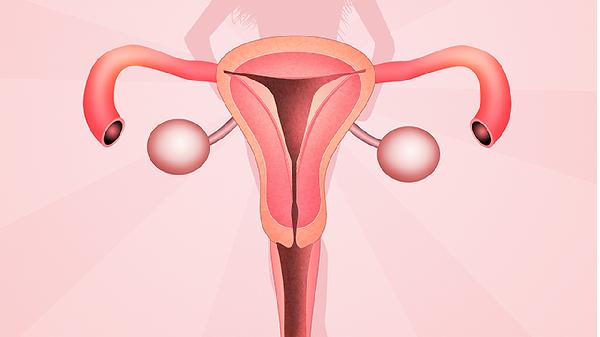

子宫畸形怀孕会胎停吗

子宫畸形怀孕可能会增加胎停的概率,但并非绝对。子宫畸形主要包括单角子宫、双角子宫、纵隔子宫等类型,是否导致胎停与畸形类型、严重程度及孕期管理密切相关。多数轻度畸形通过规范产检和干预可正常妊娠,严重畸形或合并其他高危因素时风险较高。单角子宫或双角子宫可能因宫腔空间不足或血流供应异常影响胚胎发育,尤其在妊娠中后期易出现胎儿生长受限。纵隔子宫若隔膜较厚可能干扰胎盘...